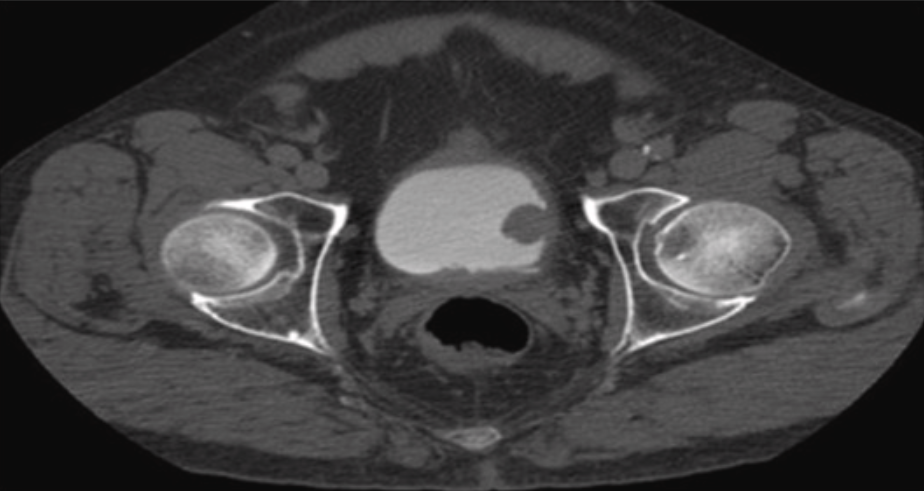

Computed tomography (CT) scans allow radiologists to identify masses in the bladder and to assess structural abnormalities in this organ9. Doctors may also perform a cystoscopy, a procedure that involves inserting a thin tube with a camera through the urethra, to examine the bladder's inner lining and capture bladder polyps images10.

What Does a Cancerous Bladder Look Like?

Malignant bladder tumors often look like irregular lumps or thickened areas on the bladder wall that stand out after contrast dye is used in scans. In more serious cases, they can spread into nearby tissues.

Radiopaedia.org provides scan images of bladder tumors at different stages. Use your mousewheel to scroll through different images from the same scan.